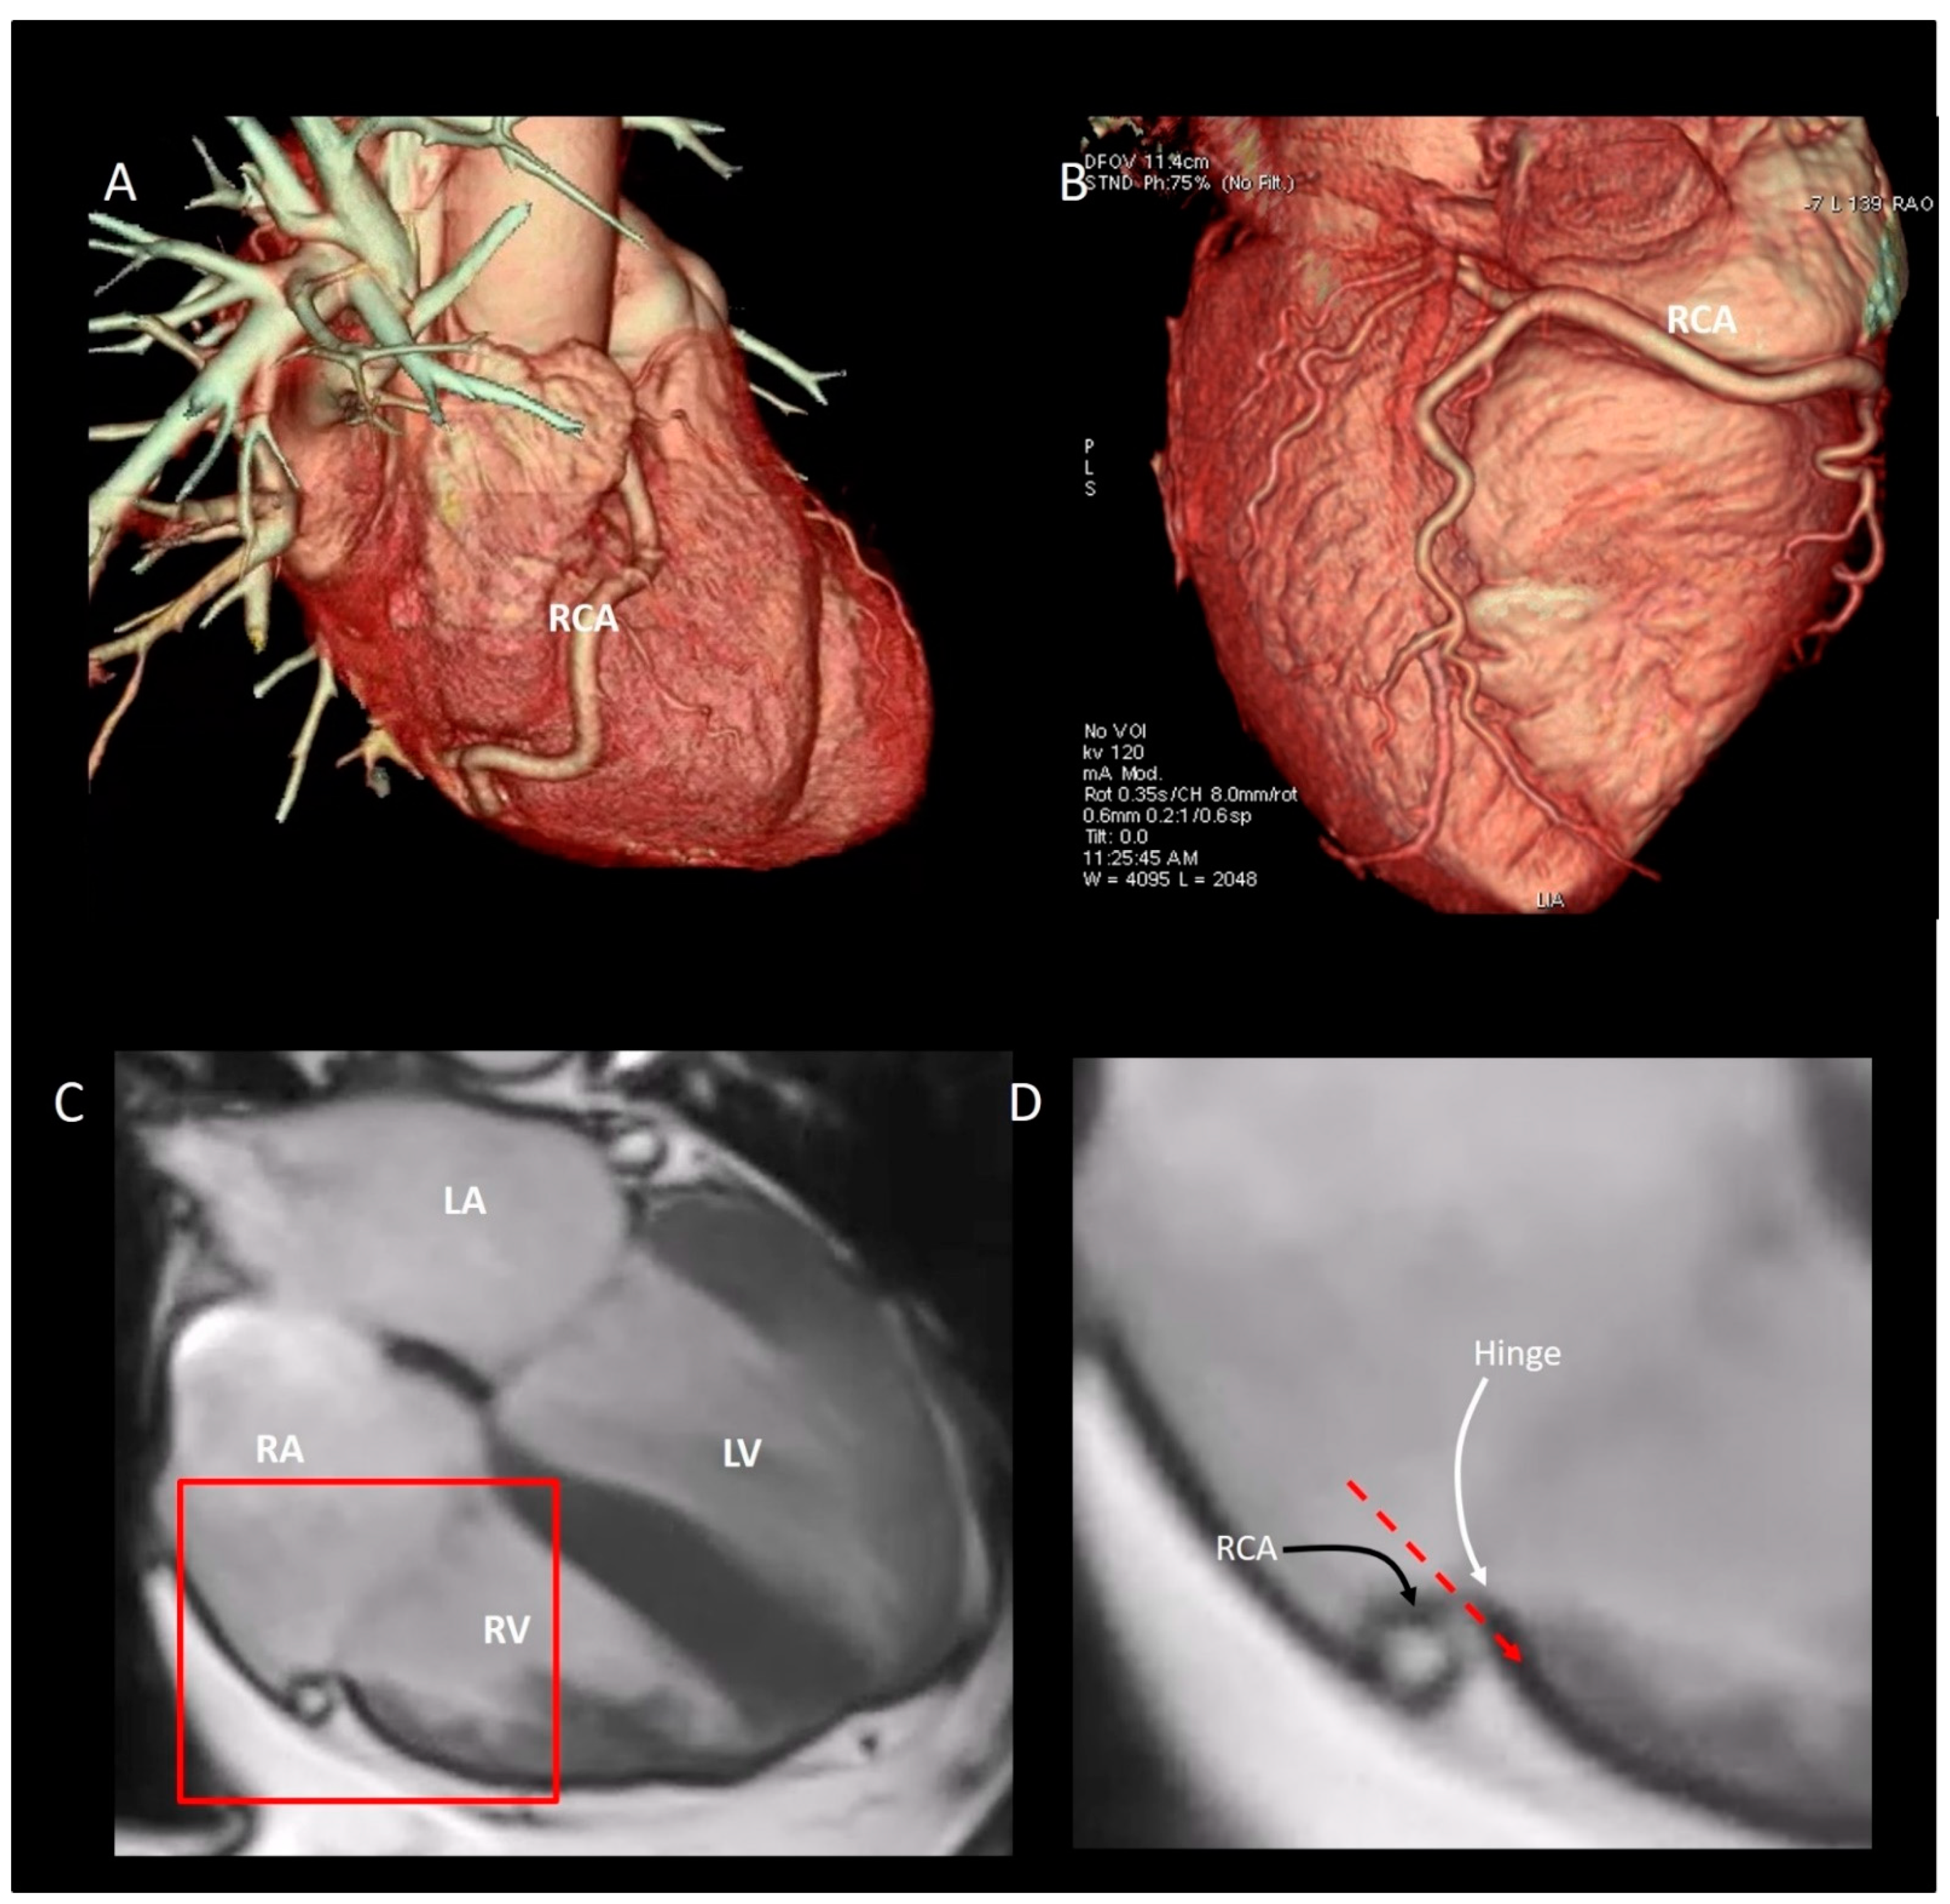

The “Mural” Annulus

4. The “Septal” Annulus

5. Physiological and Physiopathologic Consequences of the Annular Structure